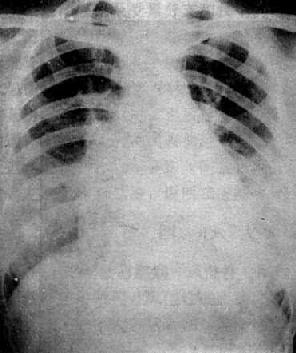

图3-2-22 Fallot四联症

心增大,心尖圆钝上翅,心腰平直,右心室增大,

肺门缩小,肺纹理纤细,稀少